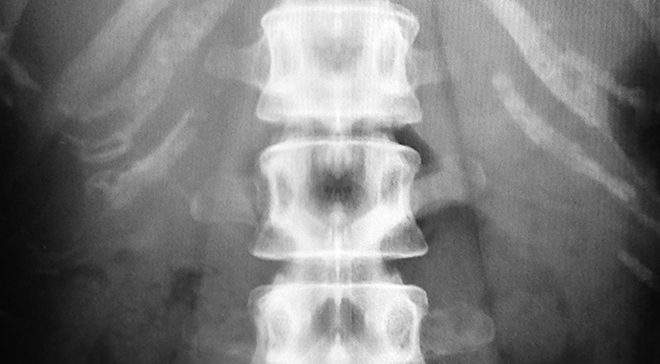

必要に応じてX線、骨密度、超音波などの検査を行います。

患者様に合わせた専門的な検査を行いますので、具体的な痛みや、身体的な問題の原因追及を行います。

エックス線検査